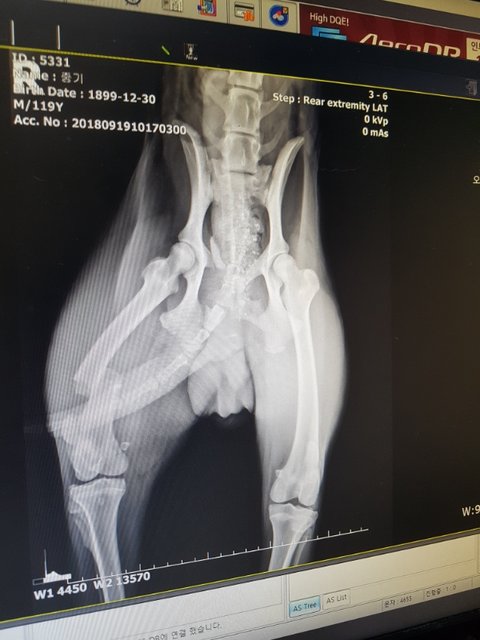

역시나 다발성 골절..

골반뼈와 오른쪽 뒷다리가 부러져 있었습니다